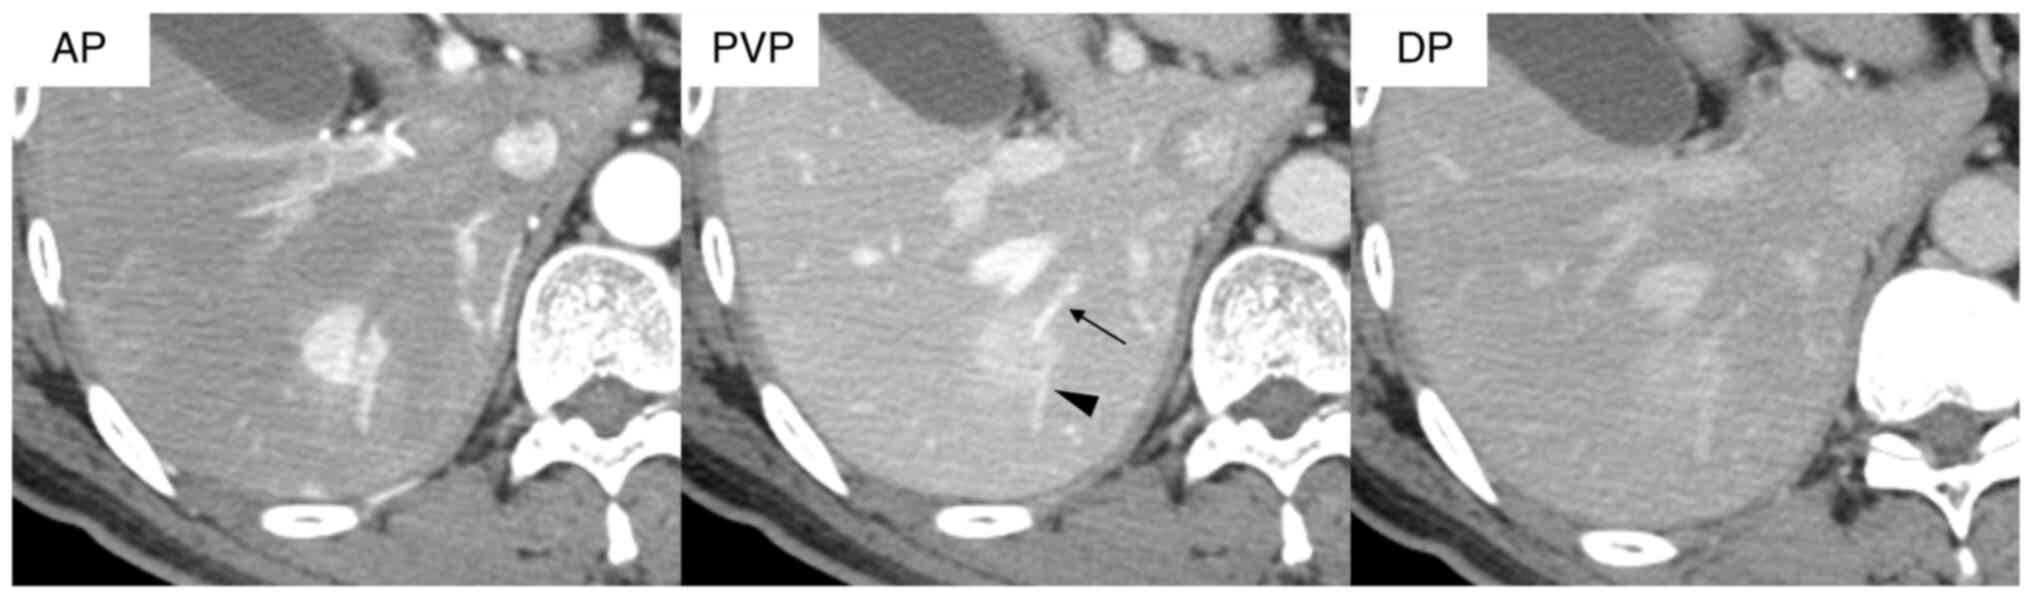

Kozaka K, Matsui O, Kobayashi S, Koda W, Minami T, Kitao A, Inoue D, Yoneda N and Yoshida K: Dynamic CT findings of cholangiolocellular carcinoma: Correlation with angiography-assisted CT and histopathology. Abdom Radiol. 42:861–869. 2017. View Article : Google Scholar : PubMed/NCBI

Asayama Y, Tajima T, Okamoto D, Nishie A, Ishigami K, Ushijima Y, Kakihara D, Aishima S, Taketomi A and Honda H: Imaging of cholangiolocellular carcinoma of the liver. Eur J Radiol. 75:120–125. 2010. View Article : Google Scholar